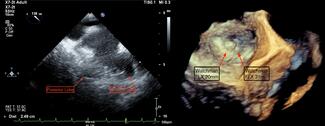

The authors report the case of an 88-year-old woman with paroxysmal atrial fibrillation, sick sinus syndrome status post-permanent dual chamber pacemaker, elevated thromboembolic risk, severe aortic stenosis, and a history of bleeding that...